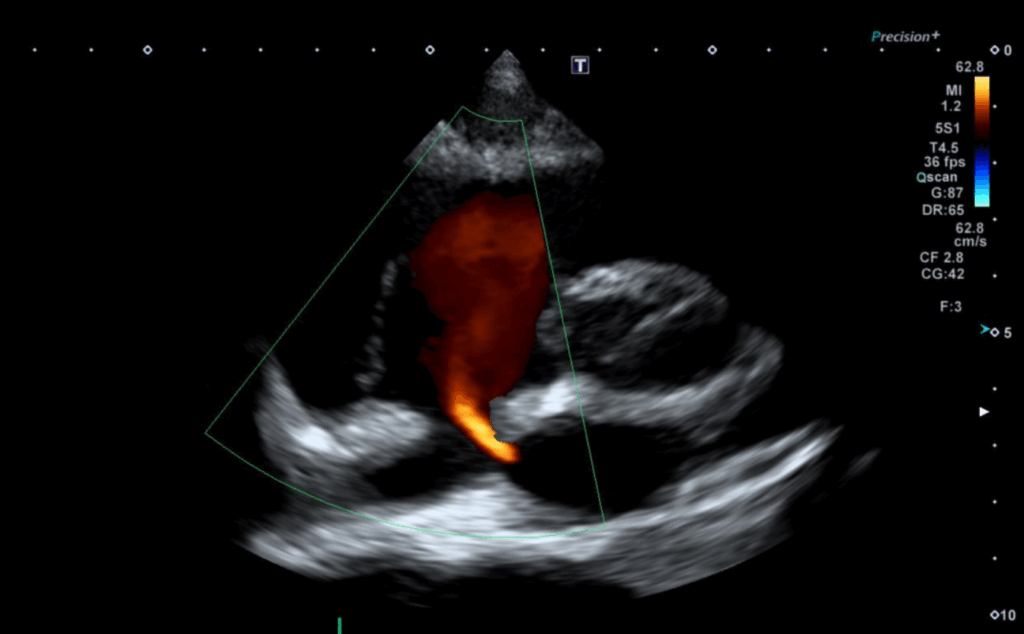

심초음파에서 좌심방과 우심방 사이에 막혀있어야 하는 중격 부분이 막히지 않아 붉은색 혈액 흐름이 관찰되었고 심방중격결손으로 판단했습니다. 환자분은 이전에 선천성 심장 이상소견에 대해 알지 못하는 상태이므로 대학병원으로 진료 연계를 진행하였습니다.

• 심장초음파 심장초음파

• 좌심방과 우심방 혈류 이동 관찰 좌심방과 우심방 혈류 이동 관찰